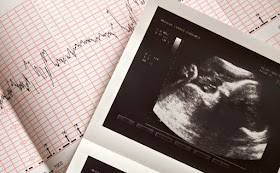

Planned Parenthood sues Iowa for banning abortion of babies with beating hearts

Planned Parenthood and the American Civil Liberties Union (ACLU) are suing Iowa over its law prohibiting abortions on most babies with detectable heartbeats, which is slated to go into effect on July 1.